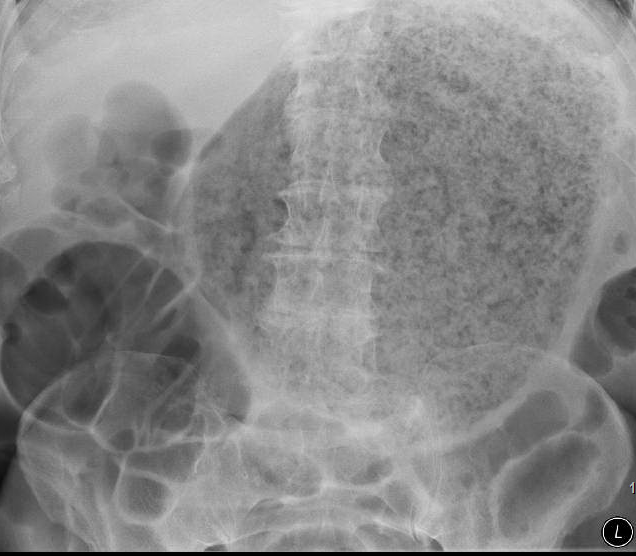

464) A 68 year old man with history of Diabetes Mellitus type II and diabetic gastroparesis is evaluated in your office for lack of appetite, nausea, vomiting, weight loss and a feeling full after eating small amounts of food material. He has lost 10 lbs weight in past 2 months. He denies any rectal bleeding or melena. He does report some epigastric discomfort. On examination, he appears in no distress, blood pressure is at 120/80. Abdomen is mildly distended with slight tenderness in upper abdomen. Patient is admitted and started on IV hydration. A plain X-ray abdomen is shown below. Gastroenterology is consulted and an upper endoscopy is pending. What is the most appropriate evidence-based next step?

A) Arrange for Laparoscopy

B) Endoscopic removal

C) Give Coca-Cola

D) Give Pepsi or any other soda

E) Metoclopramide

Filed under: USMLE STEP III QUESTION BANK, USMLE Test Prep | Tagged: ARCHER GASTROENTEROLOGY, USMLE STEP 3 GASTROENEROLOGY | 21 Comments »